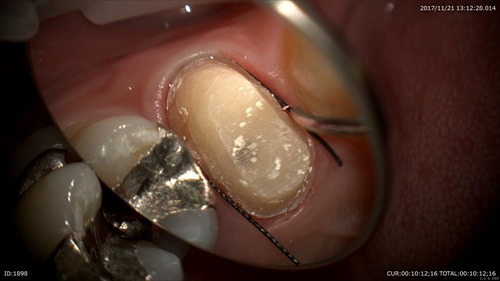

型取り。型を採るときにもこの様に糸を歯茎の境目にいれますがマイクロがないと無理に押すので痛いです。無痛治療にの為に必須!